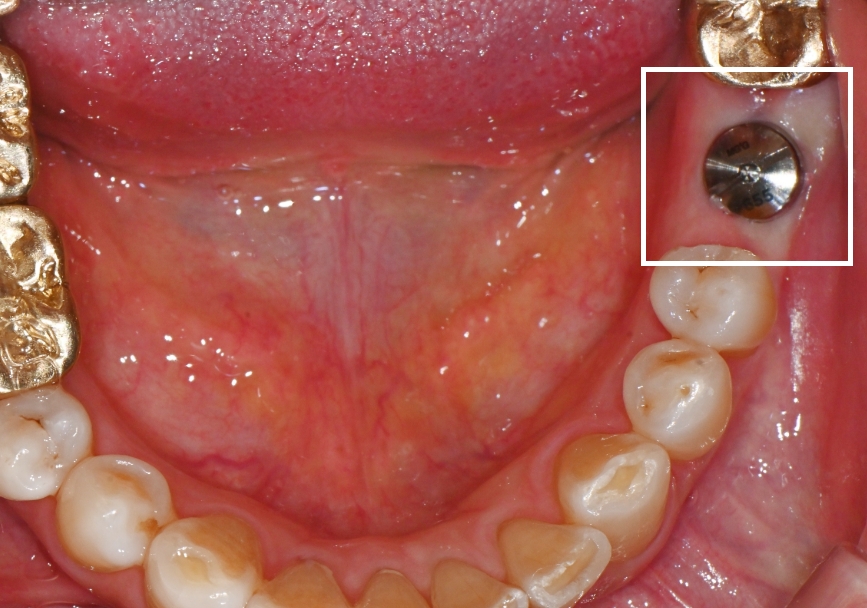

0250대 남성, 전체 임플란트 (하악)

2023.08.29 ~ 2024.04.02